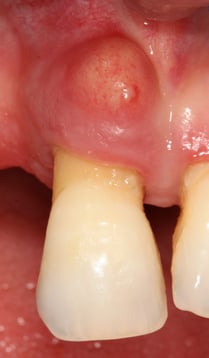

L'abcès parodontal consiste en un gonflement de la gencive lié à une accumulation de pus sous les tissus superficiels.

Selon la classification des maladies parodontales, l'abcès parodontal est caractérisé par diverses combinaisons des caractères cliniques suivants : douleur, tuméfaction, modification de la couleur de la gencive, mobilité dentaire, extrusion de la dent, suppuration, évolution étendue vers le sinus, fièvre, adénopathie, radioclarté de l'os alvéolaire affecté. Tous ces facteurs ne doivent pas nécessairement être réunis. La lésion peut être de courte ou de longue durée.